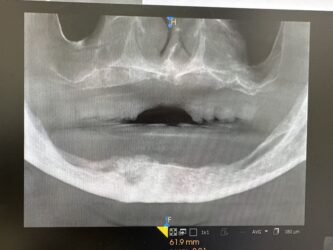

Dr. started the discussion #20 implant in the forum Complications 8 months ago

Hi, this implant was placed in June 2024. I have 3PAs (one from day of placement, one month later, and 9 month later). The intraoral picture of the soft tissue is from yesterday and tissue looks great… patient has no discomfort/pain either. She did have some discomfort between 2-3rd week after placement but subsided after taking…